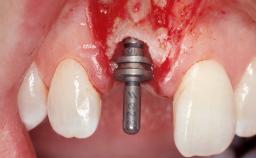

A 29-year-old female patient presented for treatment to replace the upper left central incisor tooth with an implant- supported restoration. The tooth had been intermittently symptomatic for the previous 12 months. The tooth had originally suffered trauma about 15 years previously. Several endodontic treatments had been performed, including an apicectomy procedure to retain the tooth. The patient was healthy and a non-smoker. She had reasonable expectations in regard to esthetic outcomes and the risk of marginal tissue recession following treatment. At medium smile, the gingival margins of the upper teeth were visible, with a display of 3 to 4 mm of the gingival margins. Gingival recession of tooth 21 and a discrepancy in the gingival levels between teeth 11 and 21 was observable during normal speech and smile.

| Placement Protocol | Immediate implant placement |

| Tooth Site | Maxillary incisor or canine |

| Socket Morphology | Single-root socket |

| Socket Integrity | Damage to one or more bone walls |

| Bone Volume | Damage to one or more socket walls |